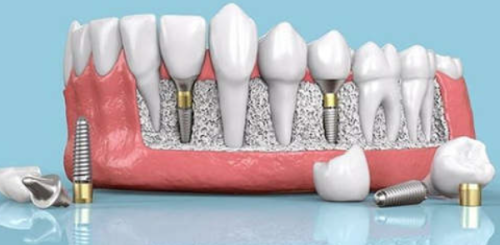

活动义齿一般多少钱一颗费用?2026年最新价格揭秘! 文章揭秘2026年活动义齿最新价格。通常镶活动假牙一颗1000 - 3000元,不同类型费用有别。如隐形义齿1000 - 1200元,便宜但寿命短、咀嚼差;钴铬合金等1500 - 2000元,强度好、使用久;纯钛基托2000 - 3000元,舒适美观。此外,地区、医院等级和医生水平也影响价格,选义齿要综合考量。 活动义齿 2026年03月04日 0 点赞 0 评论 7 浏览

活动义齿哪种最舒服还不伤害基牙?揭秘3种最佳选择! 本文围绕“活动义齿哪种最舒服还不伤害基牙”展开。首先强调了活动义齿舒适与护基牙的重要性,接着介绍了纯钛金属基托活动义齿等三种义齿的特点,包括舒适度、对基牙的影响、价格等。还给出选择建议,要考虑口腔状况、经济因素,并听取医生建议。最后提醒佩戴后注意适应期、清洁和饮食,综合考量选适合自己的义齿。 活动义齿 2026年03月04日 0 点赞 0 评论 12 浏览

补一颗活动义齿多少钱?揭秘真实费用与选择技巧! 本文围绕补一颗活动义齿的费用及选择技巧展开。费用大致在100 - 300元,受材料、修复难易、医院级别、当地经济等因素影响。不同材料义齿各有特点和价格区间。选择时要综合自身情况,选正规机构,多对比。此外,后期维护有成本,需正确佩戴清洁。提醒大家综合考量价格、质量和舒适度,必要时咨询医生。 活动义齿 2026年03月04日 0 点赞 0 评论 7 浏览